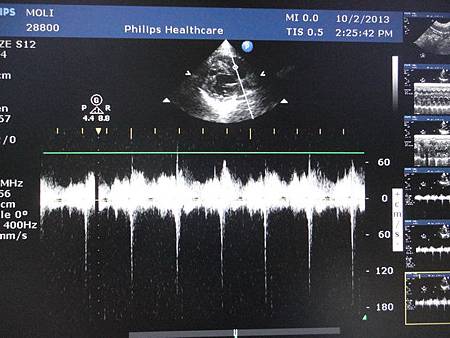

另外還有看了一下心臟,之前都還好的心臟,有出現逆流的狀況

但還不需要吃藥(鬆口氣)